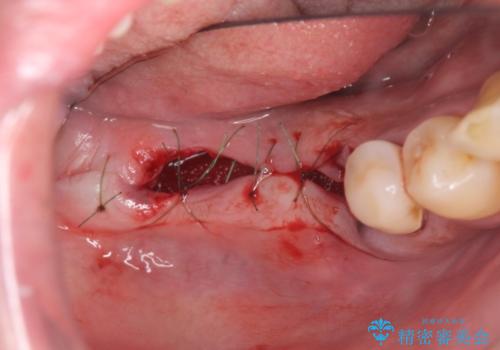

長期的な予後の見込めない奥歯の抜去を行い、骨と歯ぐきの治癒を待ち、インプラント治療を計画します。

インプラント周囲には骨の増生を埋入時に同時に行っています。